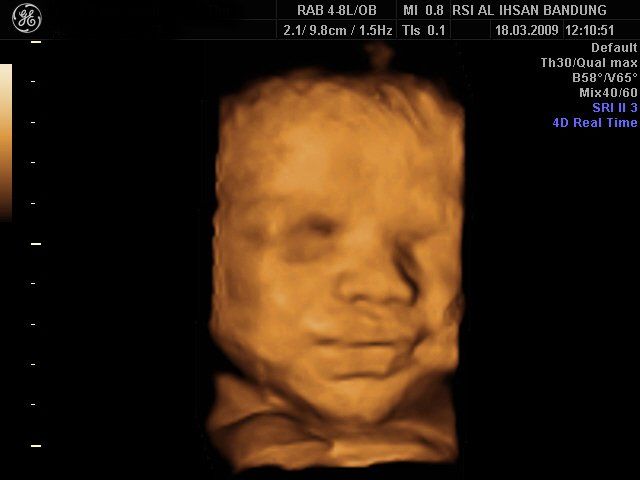

4D image of 29 weeks pregnancy, multiple anomalies: Clinch hand, omphalocoele, single atrium